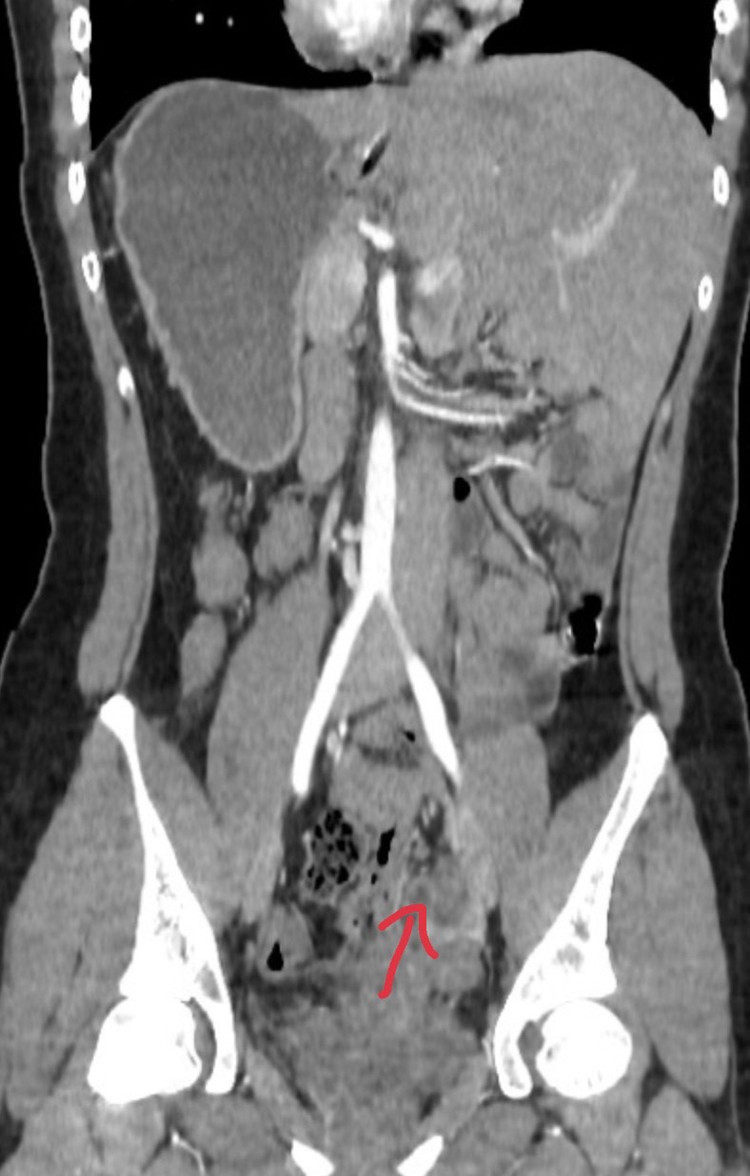

Qua khám lâm sàng và kết quả các xét nghiệm, siêu âm bụng, chụp CT ổ bụng, các bác sĩ đã xác định người bệnh bị viêm phúc mạc khu trú do ruột thừa mủ trên nền người bệnh bị đảo ngược phủ tạng hiếm gặp. Do đó, cần đưa ra phương án điều trị nhanh chóng, tránh những biến chứng gây nguy hiểm đến tính mạng người bệnh.

| Hình ảnh ruột thừa viêm ở bệnh nhân phủ tạng đảo ngược - Ảnh BVCC |

Khi vào ổ bụng, các bác sĩ phát hiện toàn bộ đại tràng, gan, lách, dạ dày, ruột thừa đều đảo ngược. Ruột thừa quặt sau manh tràng nên phải tiến hành cắt ruột thừa ngược dòng.